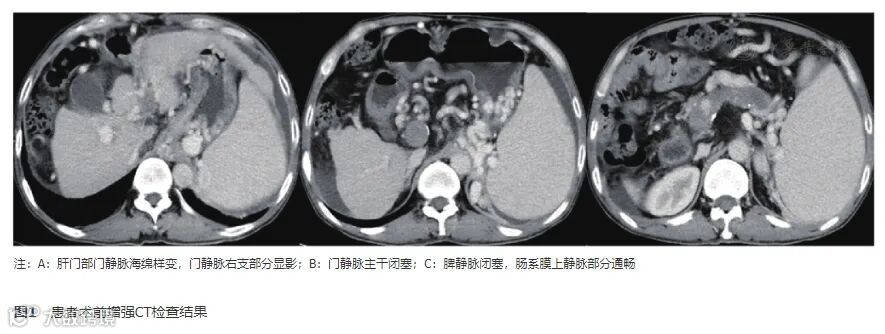

腹部超声检查见腹腔积液,下腹部最大前后径约28 mm;门静脉左右支显示不清,门静脉主干内径增宽,内可见不均回声团块充填,血流信号消失。全腹部CT平扫+增强:肝硬化,脾大伴脾内钙化灶;腹盆腔积液;门静脉高压,门静脉主干及左右分支、脾静脉栓子形成,肝门部海绵样变性,门静脉主干及脾静脉闭塞;食管胃底、脾门处静脉增粗迂曲;部分肠管管壁增厚水肿(图1)。胃镜检查见食管中下段、胃底、胃体重度静脉曲张,食管见排胶溃疡改变(图2)。